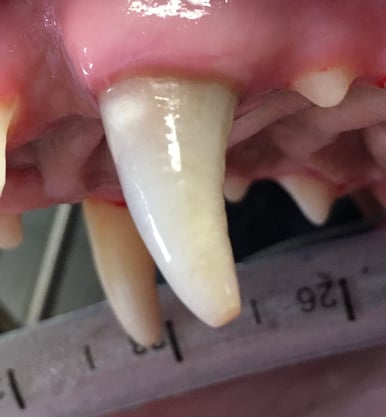

Below: (left) Close up of non-vital 204 before RCT (right) Close up of non-vital 204 after RCT

*Note that performing root canal therapy cannot remove all of the staining located in the dentinal tubules.

%20-%20March%202024/Image%20of%20204%20after%20RCT.jpg?width=386&height=418&name=Image%20of%20204%20after%20RCT.jpg)

%20-%20March%202024/current%20pic.jpg?width=386&height=510&name=current%20pic.jpg)

Tucker is thriving at home! At 7 years old, he hasn't slowed down one bit. Being a beloved pet of the ADRS staff, we get to see him frequently. Although his tooth will always remain discolored, he is pain-free and undergoes annual anesthetic dental procedures to ensure there are no issues with his previous root canal therapy.